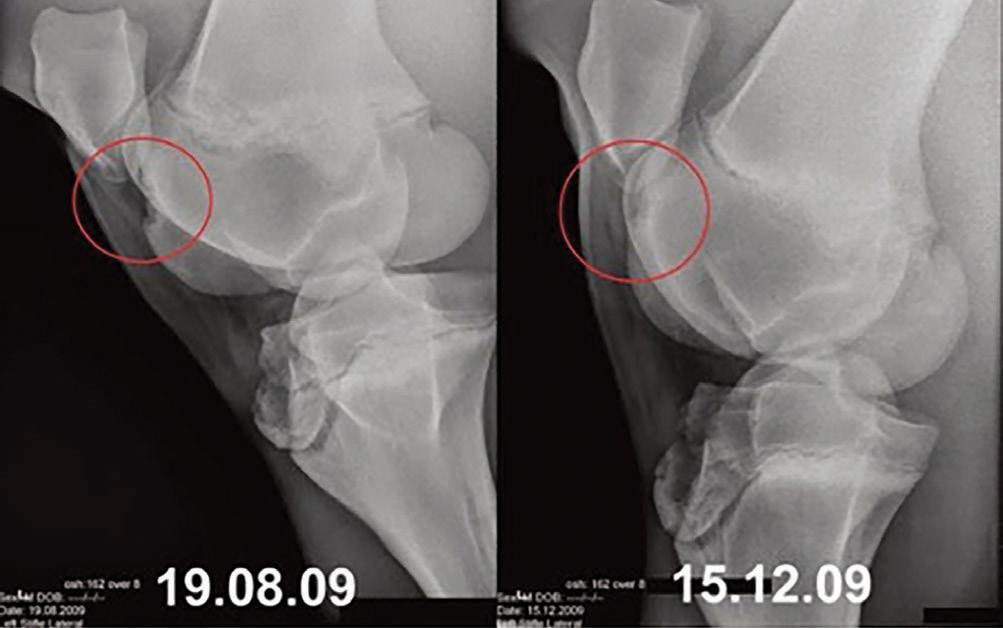

Growing up in the lush Puerto Rican mountains surrounded by coffee farms and agriculture for as far as the eye could see, Alberto Rullan seemed destined to have an equine concentrated life. Horses were used for pleasure, work, transportation and while riding horses on the roadside was not an uncommon practice, the injuries that coincided with such traveling routines were in fact inevitable.

As an eight-year-old boy, Rullan had a stallion sustain serious injuries to both hind legs and by the time they were able to track down a vet, the stallion would ultimately be put down. This devastating event marked the exact moment when Rullan would decide to dedicate the rest of his life to horses, with an emphasis on leg injuries, or lameness. How did this single moment in Puerto Rico transform and evolve into one of the most successful Equine Performance Veterinary Clinics in the country?

Rullan: I began Performance Equine Veterinary Services in 2009 and I started this rehab center in 2017. I was a lameness vet prior to opening this center in Ocala FL. My practice focuses on treating and preventing performance-related injuries in horses. I am continuously studying and

researching equine rehabilitation, lameness diagnostics and treatment therapies, particularly the use of stem cell and regenerative therapies for equine injury treatment and recovery.

H&S: What therapies do you offer at your practice and which seem to be the most popular?

Rullan: We offer a wide range of therapies and treatments, from surgery, to hyperbaric oxygen therapy, to an equine swimming pool, to electromagnetic pulse therapy, to laser therapy and so much more.

H&S: How often are you doing PRP, stem cell and injections and what are the benefits of both?

Rullan: We deal with PRP (Platelet Rich Plasma), stem cell, and injections

daily except for on Sundays. PRP is a regenerative medicine treatment that delivers a high concentrate of platelets of blood plasma to a lesion, increasing the amount of growth factors in the site to heal the area. PRP has definitely become more popular and we have had great results from this treatment.

H&S: How does the hyperbaric chamber work and what sort of benefits come from using this machine?

Rullan: This chamber increases stem cell production by 100%. If I have a horse with a bad fracture or injured tendon, we would use the chamber and we would see tremendous results. The length of time and how frequently a horse might need to go in the hyperbaric chamber varies case to case.

Typically most horses will start daily for the first five sessions and some will go inside 40-50 times or as much or as little as needed.